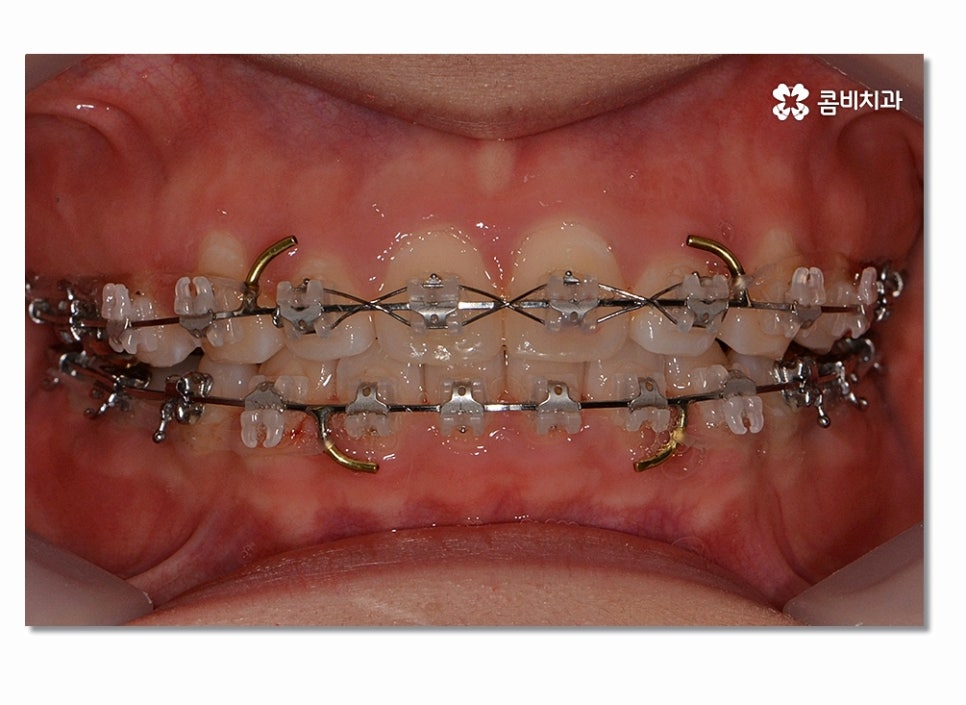

돌출입치아교정이 시작되면 이처럼 전방으로 뻐드러진

앞니를 시간이 지남에 따라서 후방으로 이동시키면서 돌출입이

점점 개선되며 이러한 치열의 변화는 교합도 잘 맞물리도록

위 사진을 보시면 치아교정 과정을 통해서 치열의 가지런함은 물론이며

측면에서 보더라도 돌출입이 많이 개선된 것을 느낄 수 있을 거예요.